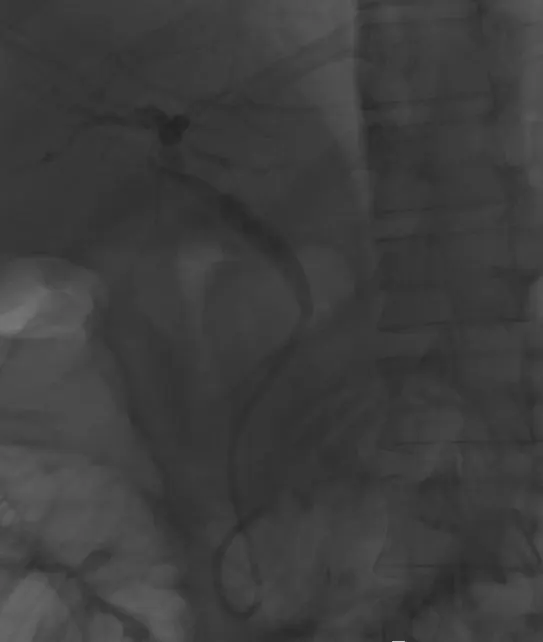

내시경이 고정되지 않았기에 간호사에게 내시경을 단단히 잡아달라고 부탁하였고, 조심스럽게 담관 입구를 찾아 카테터라고 불리는 관을 삽입하였다. 췌관과 담관은 바로 옆에 붙어 있다. 췌관을 건드릴 경우 췌장염을 더 유발할 수 있으므로 시술은 매우 조심스러웠다. 다행히 담관으로 카테터가 들어갔고, 담관을 관찰하였을 때 담관 아래쪽이 췌장염으로 인해 좁아진 것을 확인할 수 있었다.

담관을 조영하여 x-ray 로 확인하는 모습. 위쪽 담관과 비교해서 아래쪽 담관은 막혀 있다.

좁아진 담관에 스텐트라고 불리는 플라스틱관을 삽입하면, 그 관을 통해 담즙이 배출돼서 담도염이 호전되게 된다. 환자의 고통을 달래주면서 조심스럽게 담관 스텐트를 삽입하였다.

담관 내부에 플라스틱 스텐트를 삽입한 모습. 이 스텐트를 통해 담즙이 배출된다.